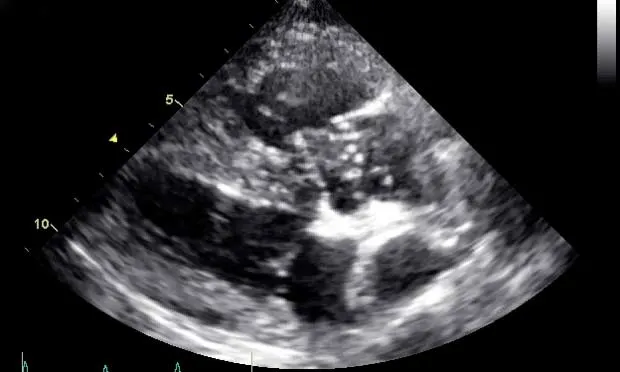

Thoracic radiography typically reveals right-sided cardiomegaly and dilated, tortuous pulmonary arteries. Echocardiography confirms caval syndrome by revealing heartworms across the tricuspid valve (Figure 1). and possibly in the right atrium, right ventricle, and vena cava. The right ventricle is usually dilated and concentrically hypertrophied. The left ventricle is small (as a result of volume underloading) secondary to diminished right-sided cardiac output.

Right parasternal transthoracic echocardiographic image showing typical heartworm echoes entwined around the tricuspid valve in the near field (arrow)